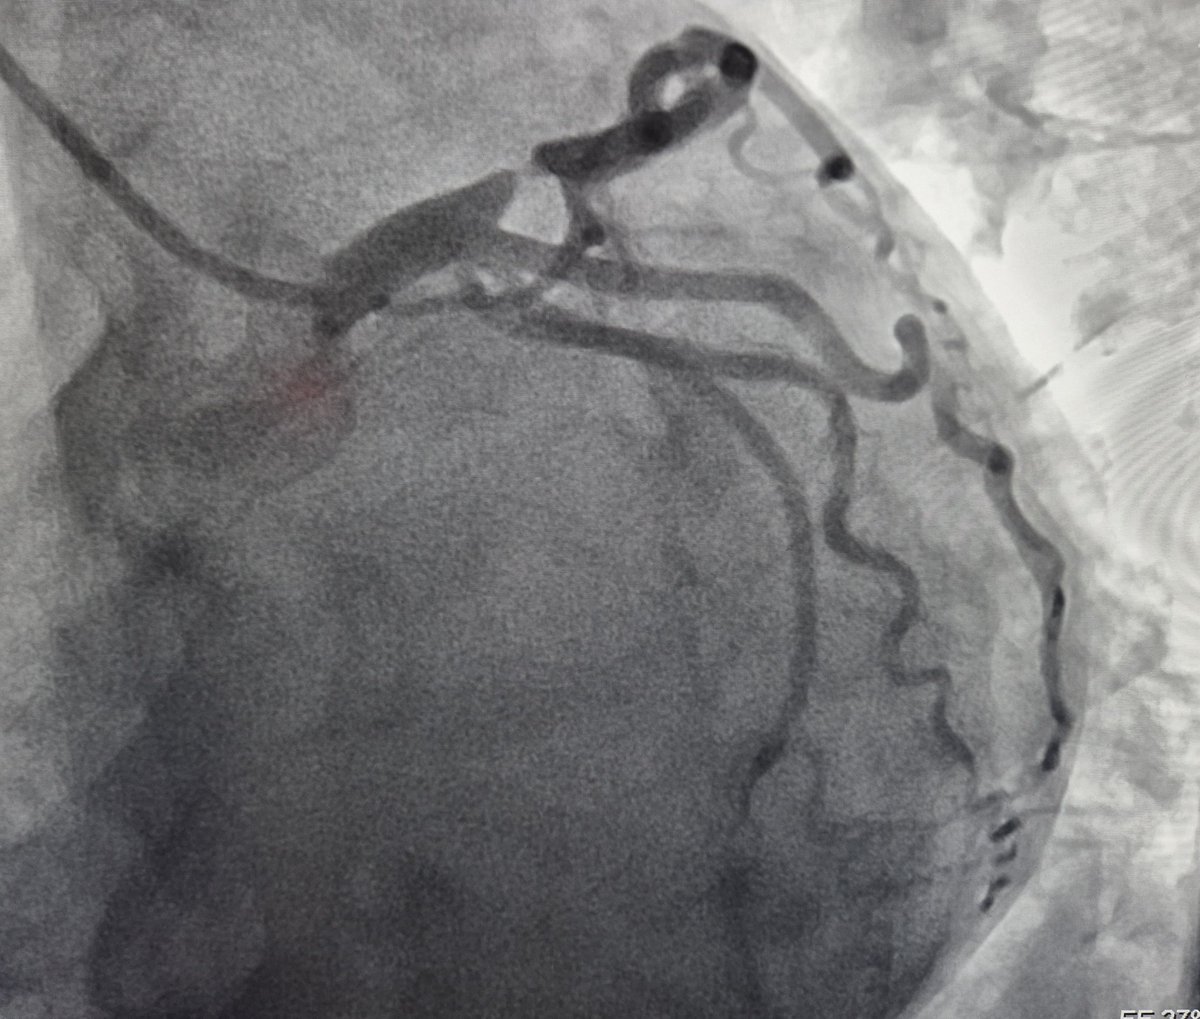

@AsherElad @PCRonline @sbrugaletta @Ortega_Paz @ANazmiCalik @Guilbom @hect2701 @NicolaRyanI1 @DrPascalMeier @w_jyg @ICigalini @Hragy From another angle

A 63 y.o female presented with NSTEMI. One year before CTA with normal LAD/RCA and mild lesion in OM1. Here is the angio and OCT images. What would you do?